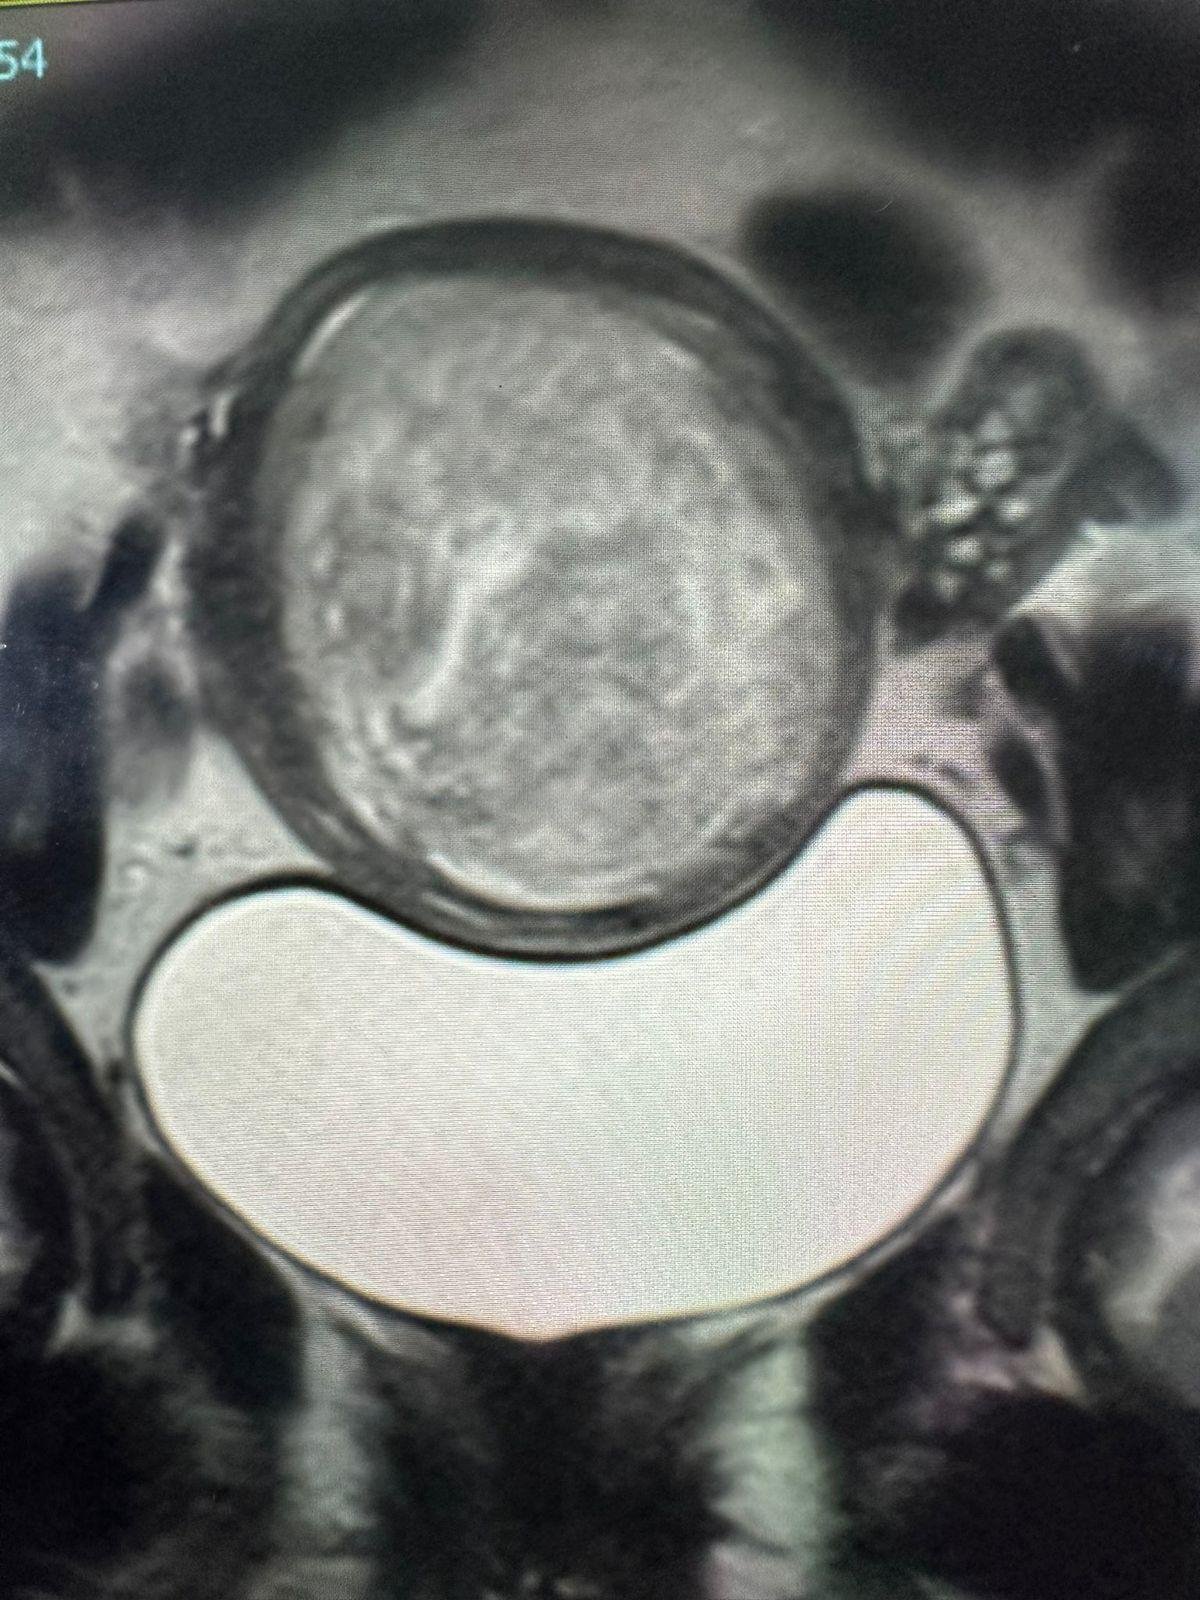

سجّلت مدينة الملك سعود الطبية قصة نجاح متميزة في علاج ألياف الرحم باستخدام تقنية القسطرة، وذلك عبر فريق الأشعة التداخلية بقيادة الدكتور أديب بازهير، حيث تُعد هذه التقنية خيارًا آمنًا وفعالًا حتى للنساء اللاتي يرغبن في الإنجاب مستقبلًا.

فقد استقبل الفريق الطبي حالة لسيدة كانت تعاني من ألياف رحمية كبيرة أثّرت على حالتها الصحية وفرص الحمل. وبعد تقييم دقيق، تقرّر علاجها بالقسطرة قبل عامين، وقد تكلّل العلاج بالنجاح دون الحاجة إلى تدخل جراحي تقليدي.

وبعد عامين من المتابعة، تُزفّ البشرى بحمل السيدة وولادتها بسلام، في تأكيد على نجاح الخطة العلاجية، وكفاءة الكوادر الطبية في المدينة.